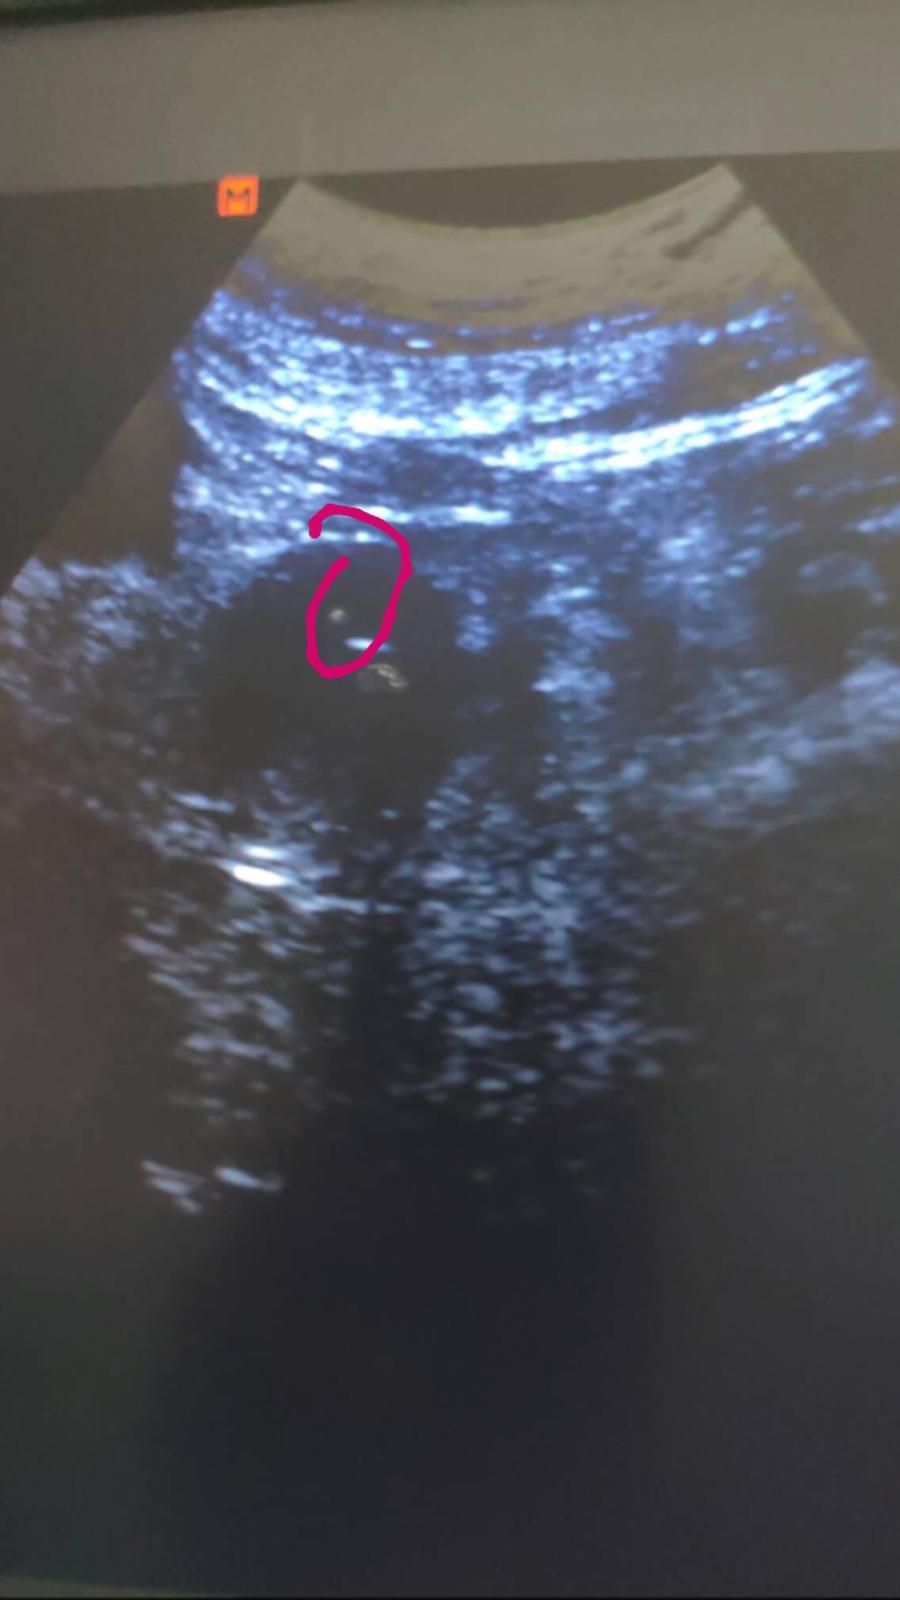

Holky včera mi bylo potvrzeno 2000hcg... Ale dneska začínám špinit 😔nevíte prosim co to může být 🙏?

@kackaa91 Kačí, to určitě nic nebude. Třeba hematom? 🤔 Volala jsi do car? Moc na tebe myslím 😘😘

@petruska23 volala sestra říkala že to může být tím že jsem měla mít menstruaci. Ale nemám za každou cenu přestávát brát prášky. Mám ležet a nemám dlouho stát... Říkala že to nic nemusí být že mám hcg krásné Tak mam byt v klidu 🙄